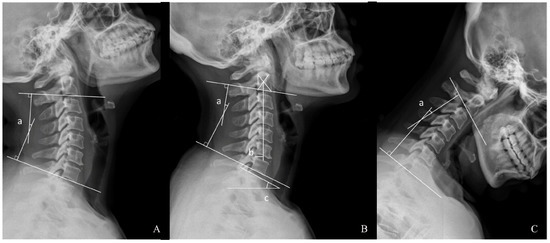

2.2. Radiographic Assessment